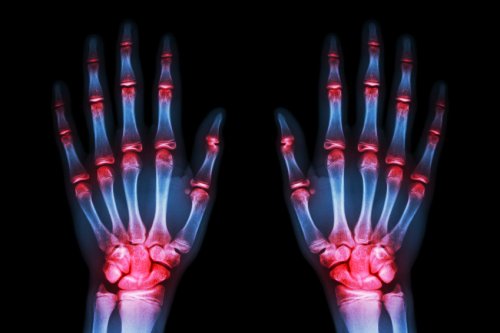

- Остеоартроз найбільше вражає руки (70%)

- Як ми знаємо, люди звертаються до лікаря в пошуках допомоги, оскільки більше не можуть витримувати біль. Біль у руках жахливий, вони німіють уночі, а також з’являються невеликі деформації.

- Коли хвороба на цьому етапі, її неможливо сповільнити. Тому ключовим є якнайшвидше визначення ознак остеохондрозу.